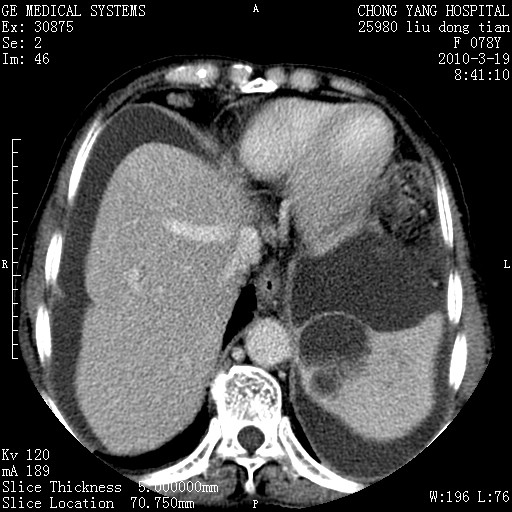

标题: CT25199:F 78Y 腹胀半年 消瘦乏力 [打印本页]

胆囊壁增厚并明显强化,胆囊癌伴多发转移瘤可能性大,淋巴瘤不除外,右肾囊肿,胸腹水.

考虑nhl,肝、脾、腹膜腔及腹膜后多发淋巴结受侵,腹水,右肾囊肿,慢性胆囊炎,右侧少量胸腔积液。

胰头有肿块形成,胰头ca伴肝脾、腹膜腹膜后转移

胆囊有软组织影有强化,支持胆囊癌,肝脾、腹膜后淋巴结转移。

nhl的淋巴结多围绕主动脉,而且主动脉会移位,所以不考虑nhl。

分开来讲:肝左叶、尾叶病灶有不均强化像肝癌;

肝门、胰腺头、腹膜后多个团块: 淋巴瘤,转移;

胰头ca伴肝脾、腹膜腹膜后转移!

最后报的胰头癌多发转移,脾脏单独考虑囊肿或淋巴管瘤。